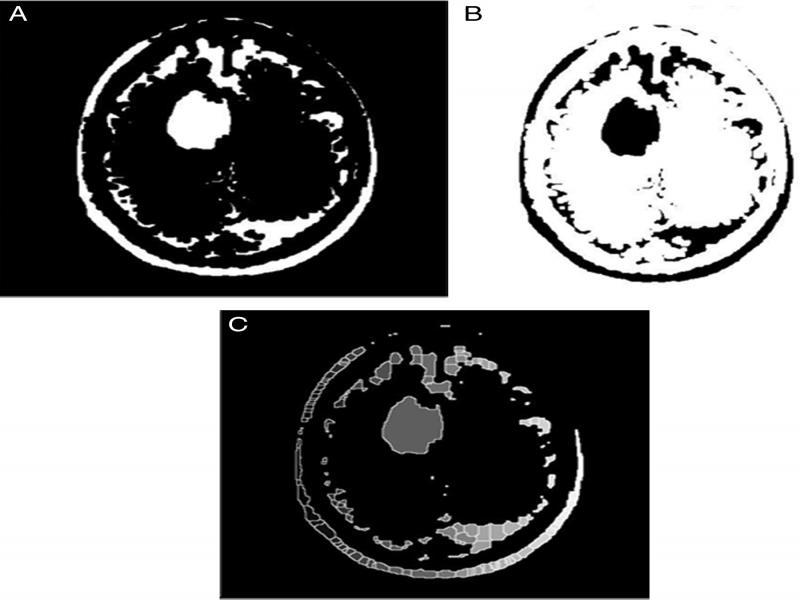

The two post-processing techniques used in the proposed methodology include k-means clustering and Maximally Stable Extremal Regions (MSER).

K-mean clustering: In k-mean clustering, the image is segmented into ‘k’ different clusters. For this procedure, the value of k is taken as 4. ‘K’ centroids are set and the clustering is done based on the least distance of a pixel from the centroid. These centroids are processed one at a time and result in the formation of 4 layers of the image containing different pixel groups. These four layers, when superimposed make the entire image.

Maximally stable extremal regions (MSER): MSER function fine-tunes the similar intensity pixels by grouping them according to intensity bands. This method is used for blob detection and connects areas of similar intensity. Thus, the detected tumor region is obtained and highlighted for better visualization (Figure 7).

Figure 7:

Post-processing (A) Image with four different coloured clusters superimposed after K-Means clustering and (B) Image after MSER detection.